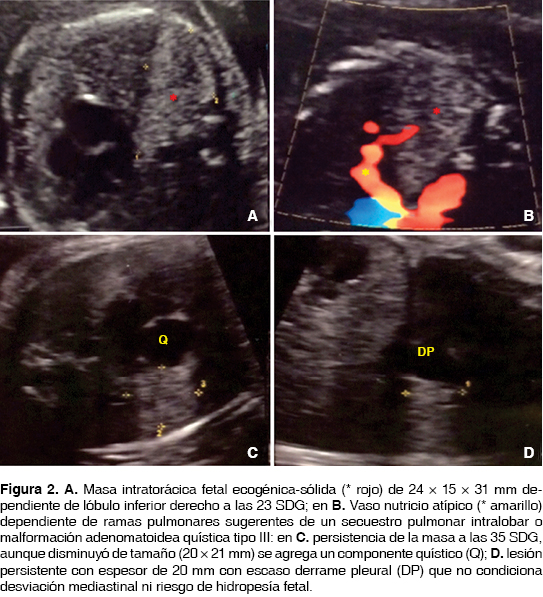

Caso 2. Feto de 23.1 SDG con una masa ecogénica en el lóbulo inferior del pulmón derecho recibiendo irrigación de un vaso nutricio aparentemente tributario de las ramas pulmonares de 24 × 15 × 31 mm, sin datos de derrame pleural ni desviación mediastinal y sin morbilidad materna presente. En un control ultrasonográfico posterior a las 35.1 SDG persiste la masa ecogénica con un componente quístico agregado de 20 × 15 × 20 mm con aparente disminución de tamaño, pero persistiendo con la misma irrigación aberrante ya descrita compatible con secuestro pulmonar intralobar y probable malformación adenomatoidea quística, sin desplazamiento mediastinal y con una relación lesión/circunferencia cefálica (CVR) de 0.1 traduciendo riesgo bajo de desarrollar hidropesía fetal, sin datos de morbilidad materna (figura 2).